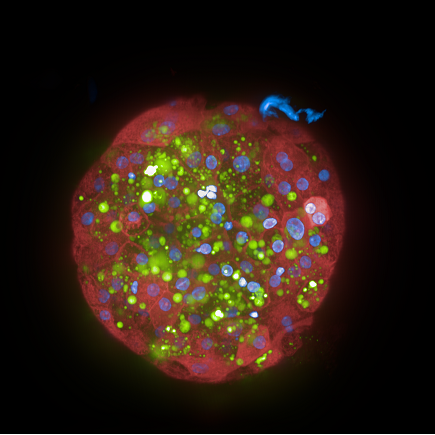

Human Liver Microtissues from InSphero labeled with Hoechst (nuclei, blue) and CellMask™ Deep Red plasma membrane stain.